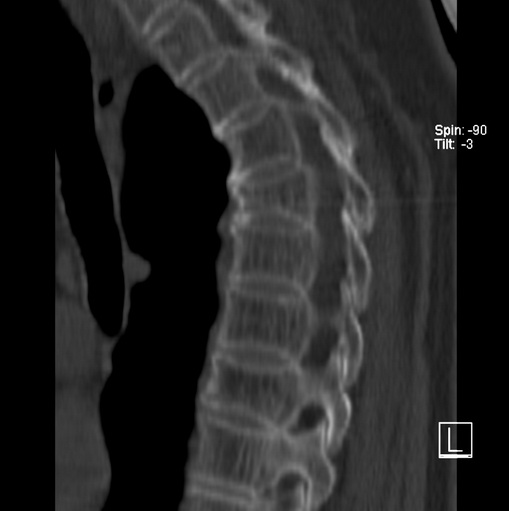

标题: CT25377:脊柱有无压缩骨折?

女、73、胸痛、胸闷3个月,无明显外伤病史,x线疑t4、t7陈旧压缩骨折,ct未经明显骨折,请问结论如何报?

老年女性病人,骨质稀疏,有些驼背,t4明显变扁,t7略变扁,椎体边缘无中断,骨小梁排列正常,无嵌插所致致密线。结合无明显外伤史,考虑老年骨质稀疏,慢性压缩改变,正如老年人骨质稀疏椎体呈双凹改变一样。我考虑报:老年骨质稀疏,t4、t7楔形变,脊柱曲度改变(驼背).敬请大家指教。

1)多个胸椎陈旧性压缩性骨折。2)胸椎普遍性骨质疏松。3)胸椎退行性改变。